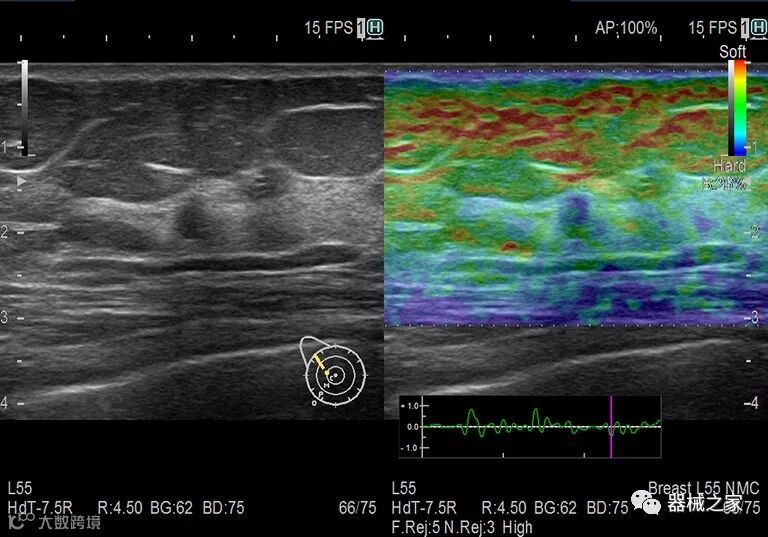

在几年前,超声波无法对小型慢流血管中的血流进行成像,但现在有少数供应商提供具有此功能的系统。该特征提供了另外一种检查病变以指示癌症或炎症的方法。其中一个是佳能Aplio 900 CV系统,它可以显示毛细血管中的血流量。日立的Arietta 65中程系统提供了一种可视化小血管的功能,可以更好地观察肾脏等器官的灌注情况。三星RS85还提供MV-Flow可视化慢流微血管结构。